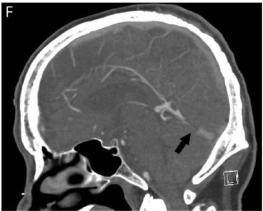

考虑到之前的影像检查未能检测出潜在的静脉血栓,我们对患者还是进行了脑血管造影检查。静脉期示直窦硬脑膜动静脉瘘(dural arteriovenous fistula, dAVF)(Borden分级 III级),直窦中段短节段闭塞。可见多重血管供应包括左侧脑膜中动脉后支、左侧大脑后动脉脑膜支以及Davidoff和Schechter动脉。经动脉栓塞后dAVF血流减少70%。经静脉未能执行是由于导管无法穿过直窦血栓,提示血栓形成是慢性形成的。

CTA和MRA被推荐用于检测dAVF,但不同研究其敏感性差异很大(MRA低于50%,CTA低于15%)。尽管一些影像征象如不对称性颈静脉衰减、动脉供血异常突出、散乱的静脉窦可将CTA的敏感性和特异性增加至>90%,但对于高度怀疑dAVF且无创影像学检查阴性者仍应进行脑血管造影,它是检测dAVF的金标准。